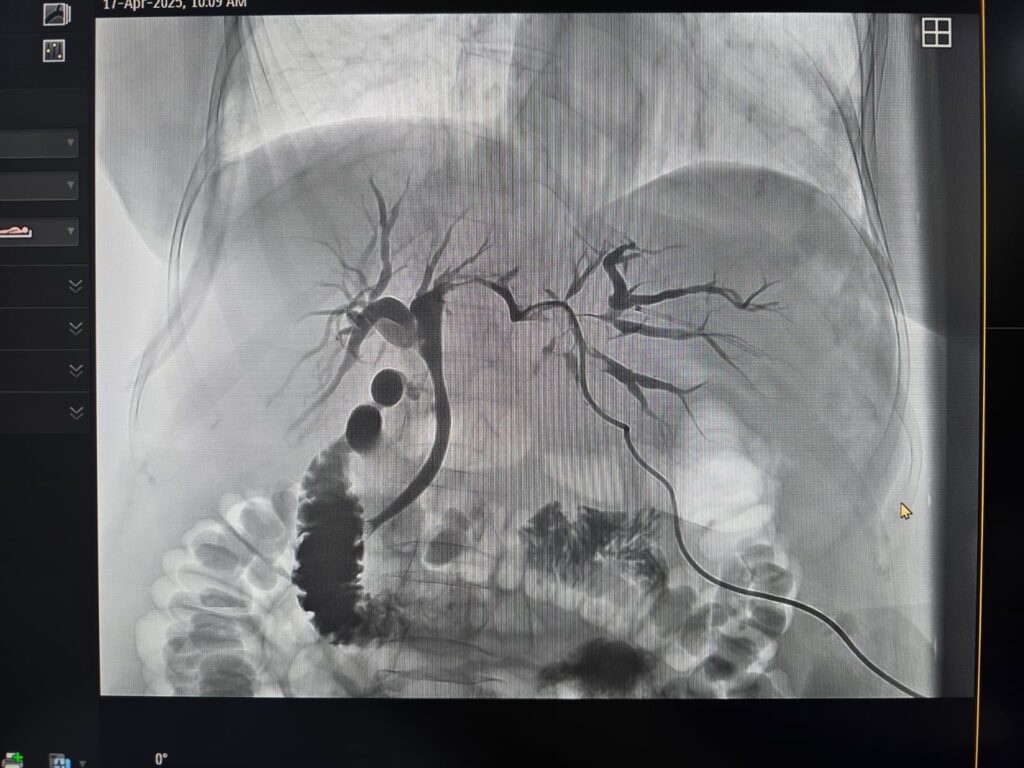

Pacienta, în vârstă de 71 de ani, cu colestază severă cauzată de o formațiune tumorală situată la nivelul hilului hepatic, a beneficiat de o abordare terapeutică multidisciplinară în două etape, în contextul unui caz considerat inoperabil chirurgical.

În prima etapă, echipa de Radiologie Intervențională a realizat cu succes un drenaj biliar percutan transhepatic. Ulterior, în a doua etapă, în colaborare cu echipa de Gastroenterologie, s-a efectuat montarea unui stent pe căile biliare extrahepatice, printr-o procedură hibridă, ghidată atât angiografic, cât și endoscopic.

Această intervenție a fost posibilă datorită dotării spitalului cu angiograful utilizat în cadrul procedurii, achiziționat printr-un proiect coordonat de dr. Florin Grosu, cu sprijinul și efortul financiar al Consiliului Județean Sibiu.